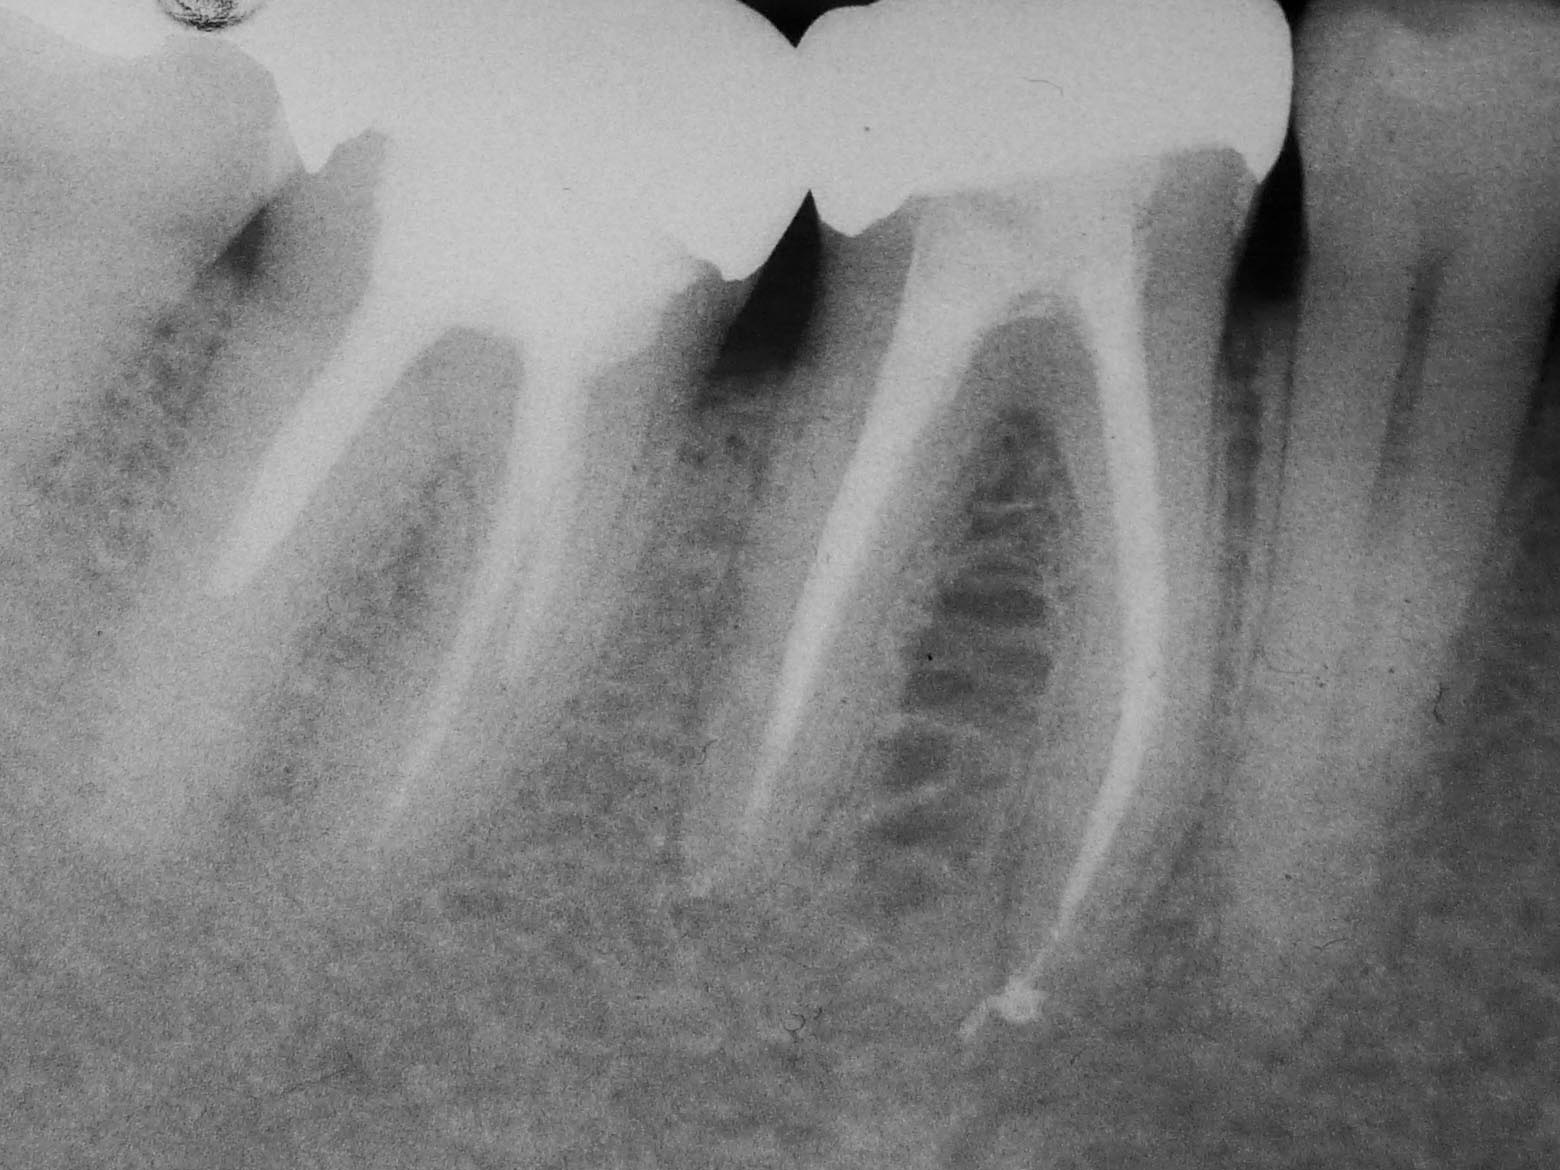

Rätselbild-6 Veröffentlicht 31. August 2009 am 1560 × 1170 in Shit happens: Das Rätselbild – Die Auflösung